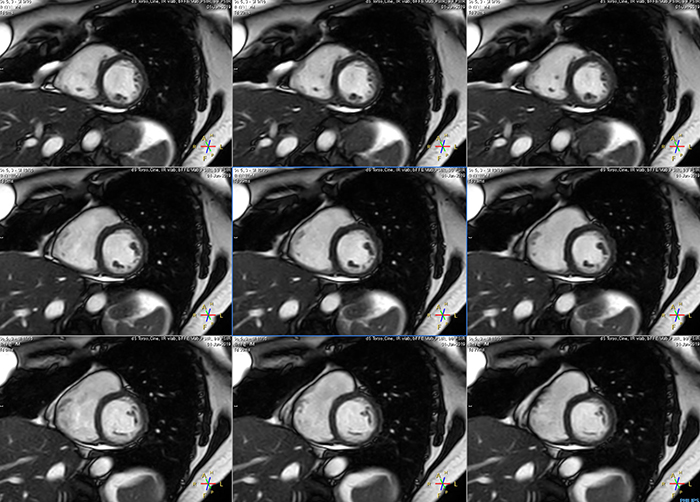

Avila says that Compressed SENSE allows them to reduce breathhold time to 3 to 4 seconds in cardiac cine scans. “At the same time, we can now – based on cardiac frequency – obtain as many as 30 to 40 cardiac phases without sacrificing resolution, while before Ingenia Ambition, we were acquiring only 20 phases.

“This ability to use Compressed SENSE for obtaining higher temporal resolution translates to a much smoother cine. This allows me to better assess heart function,” Dr. Peña says.

These are some images of a cardiac cine scan with a short breath-hold time. A high temporal resolution provides a smooth cine, which helps in assessing heart function. Ingenia Ambition.